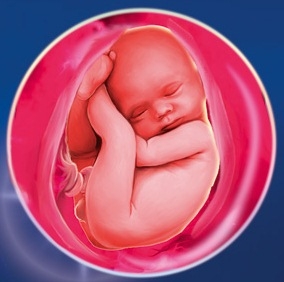

Дитина в третьому триместрі вагітності

Ваш малюк практично сформований і зараз вдосконалюються все його органи. Він росте і набирає вагу, стає активнішою і ви можете відчувати його рухи.

До кінця третього триместру малюк підростає, йому стає тісно, тому рухається він рідше, але його поштовхи сильні, а іноді і хворобливі.

Однак, якщо вам здалося, що рухи дитини стали слабкими або зовсім припинилися, терміново прямуйте до лікаря. Це може бути причиною задухи. Іноді пуповина обвита навколо шиї малюка і перекриває йому кисень. У цьому випадку ваш лікар може запропонувати стимуляцію пологів, щоб уберегти дитину. Тому ви як майбутня мама повинні дуже уважно ставитися до себе і свого теперішнього стану.